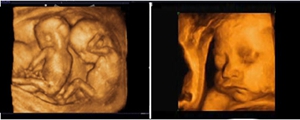

相对于单胞胎来说,双胞胎是具有一定的特殊性的,双胞胎进行四维彩超的技能难度要大于单胎。对于双胞胎四维彩超检查,泉州较多孕妈们选择福兴妇产医院,具体原因是什么呢?通过以下介绍了解下。

福兴妇产医院是较早推出双胞胎四维彩超检查的医院,在单胎检查的基础上做到判断双胎的绒毛膜性及羊膜性,因单绒毛膜囊双胎具有独特的特性,发病概率极高、预后极差的并发症如T T T S(双胎输血综合症)、双胎动脉反向灌注综合症等。

福兴妇产医院是泉州地区较早引进具有“神器彩超”之称的美囯GE E8四维彩超的医院。

美囯GE系列四维彩超以出色的成像技能、自动化辅助诊断工具、更高的硬件性能被广大孕妈和医生信赖。四维彩超能够、多角度动态显示未出生的宝宝的活动图像和人体内脏器官的图像。